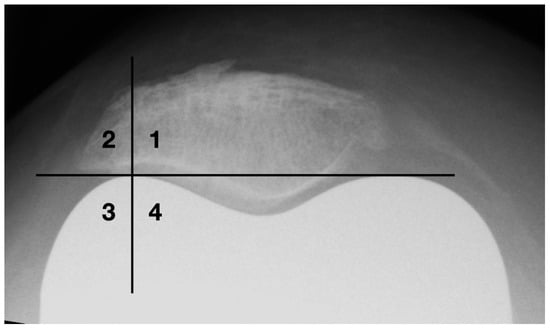

Osteophytes are one of the basic radiographic signs in osteoarthritis diagnostics [27]. During surgical joint replacement, osteophytes are usually removed. Left lateral osteophytes may lock and lead to compulsory guiding of the patella. This results in patellofemoral constraint, which is a common cause of functional limitations and postoperative pain in the femoropatellar joint [11]. A quadrant model was used to classify the lateral bony attachments (see Figure 7). The horizontal division is made at the level of the apices of the femoral condyles. The vertical dividing line runs through the center of the lateral femoral condyle.

Figure 7. Classification of osteophytes with a four-quadrant-model.